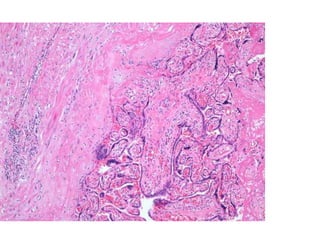

 Accreta (villi attach direct to uterine muscle)

 Increta (invade further into myometrium)

 Percreta ( through myometrium)

 Uterine atony– commonest cause  Placenta praevia  Retained placenta  Placental abruption – severe coagulopathy  Creta syndromes  Accreta (villi attach direct to uterine muscle)  Increta (invade further into myometrium)  Percreta ( through myometrium)